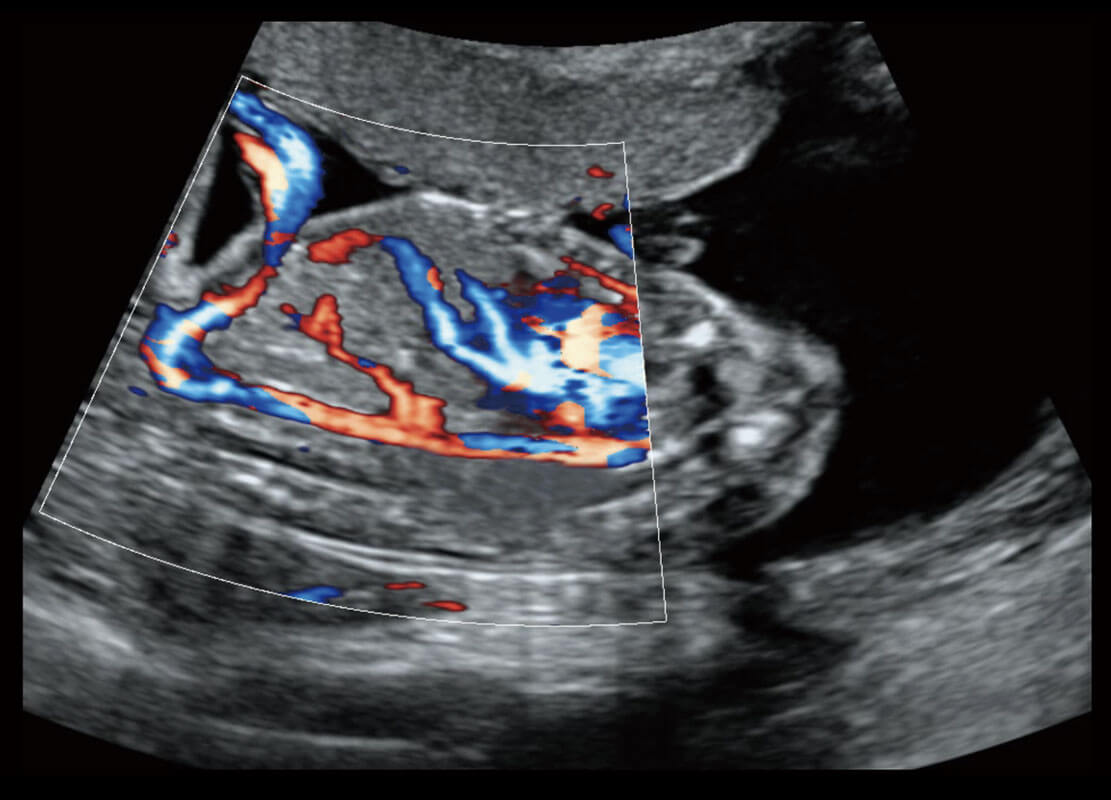

胎儿体循环